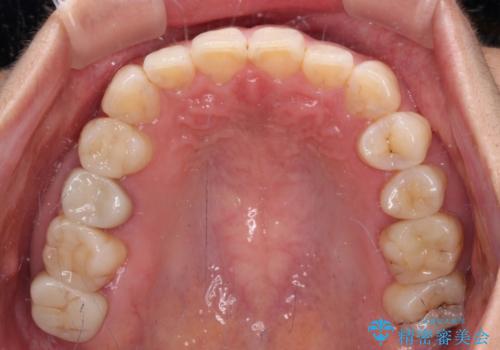

- 見た目の不揃いなセラミックと、痛みを感じる歯を気にして来院された患者様です。

右上の歯は噛んだときに何カ所か痛みを感じるとのことで、診査したところ第二小臼歯が患歯と疑われました。

患者様は他の歯にも痛みを感じるとおっしゃっていましたが、そのような所見が認められなかったため、まずは第二小臼歯を処置し、その痛みが引いた後に再診査することとしました。

痛みが引いた後、不揃いな見た目で気になっていた左下の奥歯とともにオールセラミッククラウンにて補綴治療を行うこととしました。

右上の歯は、第二小臼歯の初回処置後に痛みを感じなくなったため、他の歯については問題なしと診断しました。

将来ホワイトニングをされるとのことで、前歯よりもやや白い色合いのオールセラミッククラウンを選択されました。